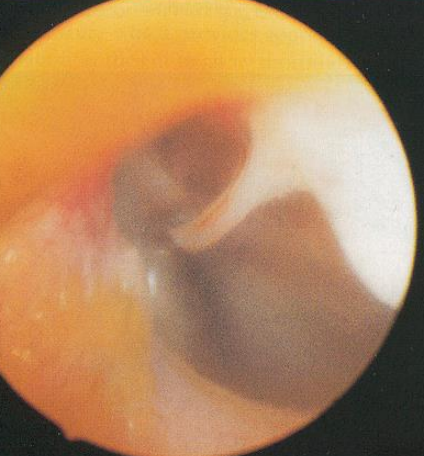

| Otoscopic examination | |

- 수직/수평귀길 상태 파악, tympanic membrane rupture 확인, mass 확인 ![]() (왼: 정상, tympanic membrane이 malleus 끝에 있음. / 중 : 비정상, rupture / 오 : 비정상, mass) | |